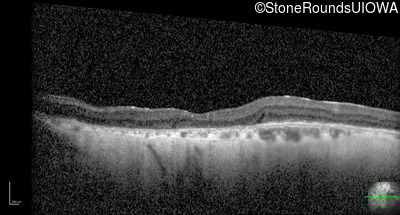

Optical Coherence Tomography - Left - 20/200

Exemplar / OCT Stack